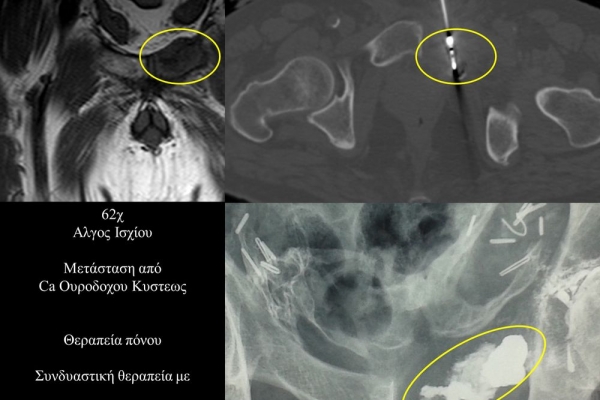

Η αντιμετώπιση του καρκινικού πόνου, εκτός από την κλασική συντηρητική φαρμακευτική θεραπεία, όταν ο πόνος επιμένει ή όταν οι παρενέργειες των φαρμακευτικών μεθόδων εξαντλούν τον ασθενή, περιλαμβάνει ελάχιστα παρεμβατικές τεχνικές με τις οποίες επιτυγχάνεται διακοπή ή καταστροφή της νευρικής οδού μεταβίβασης του πόνου. Η επεμβατική ακτινολογία διαθέτει μια πληθώρα θεραπευτικών τεχνικών που σκοπό έχουν να προσφέρουν ποιοτική βελτίωση της ζωής και των σχέσεων, τόσο των ογκολογικών ασθενών, όσο και των οικογενειών τους.